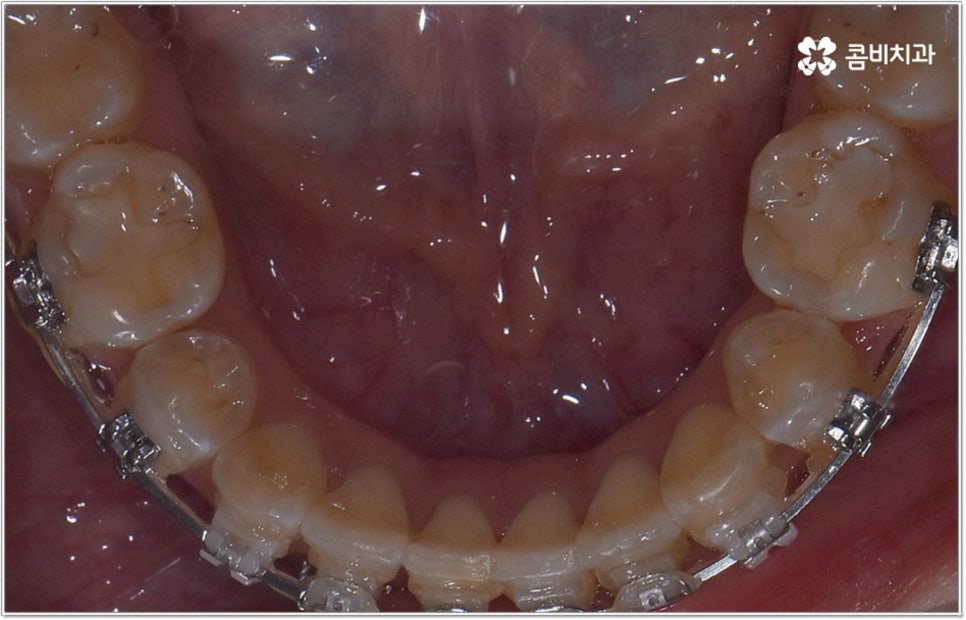

잘 아시다시피 교정이란 치아에 교정 장치 (브라켓) 를 부착하고 와이어에 교정력을 걸어 필요한 방향으로 치아를 이동시킴으로써 고른 치열과 올바른 교합을 가진 정상적인 구강 구조를 회복하는 치과 진료를 의미하는데요, 말씀드린 것처럼 부정교합에는 다양한 형태가 있고 또한 환자분들마다 심각한 정도가 모두 다르기 때문에 현 상태를 면밀하게 체크하고 맞춤 교정 치료 계획을 세우는 것이 무엇보다 중요하다고 할 수 있습니다. 즉 3D CT 와 같은 정밀 진단 장비를 갖추고 있는 치과에서 교정 관련 임상 경험이 풍부한 숙련된 의료진과 함께 치료를 진행하는 것이 필수적이라고 할 수 있어요. 전체 방향 및 세부 플랜을 세울 때 각 환자에 맞게 치아의 이동 속도에 무리가 가지 않도록 하기 위해서 연령이나 발달 상황, 진행 상황을 면밀하게 살펴보는 것이 필요하며 또한 구강 내 공간 유무 및 부정교합 정도에 따라 발치 또는 비발치치아교정 여부를 결정하게 될 거예요.

만약 치아가 이동할 범위를 계산해 봤을 때 공간이 충분하다면 굳이 치아를 뽑지 않고 비발치치아교정 과정으로 치료할 수 있어요. 제일 뒤에 있는 어금니를 더 후방으로 이동시키거나 치간 삭제, 악궁확장장치 등으로 치아 사이를 벌려서 이동 공간을 확보할 수 있으면 비발치치아교정 이 가능한 거예요. 이 때 부정교합이 심각하거나 악골이 치아에 비해 많이 작은 경우, 구조적인 원인을 개선할 필요성이 있는 경우 등 발치 교정을 하는 것이 꼭 필요한 케이스라면 치아를 뽑아주어야 하며, 환자분들의 상황에 따라 다르지만 보통은 소구치를 발치하는 경우가 많이 있습니다.